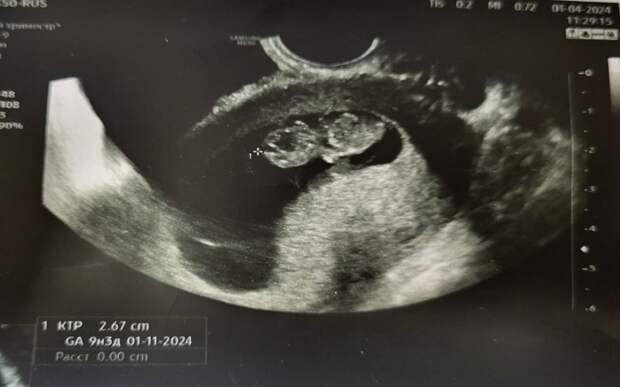

Женщину доставили в больницу с жалобами на боли в животе. Выяснилось, что пациентка беременна - при этом наряду со стандартной беременностью одновременно зафиксировали внематочную.

Женщине провели операцию, при этом маточную беременность удалось сохранить. К тому же рязанка сможет забеременеть повторно - операцию провели лапароскопическим способом, сохранив необходимые органы.